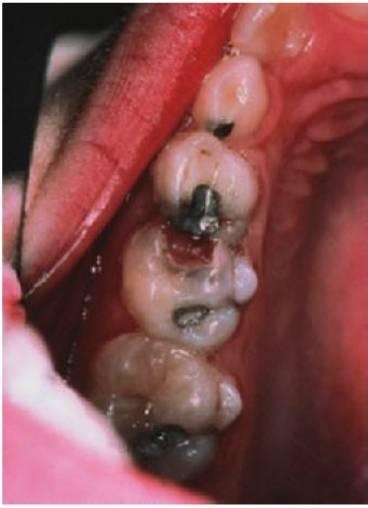

Dolor

Los pacientes más jóvenes, con frecuencia, varían al informar de su dolor y muchas veces los padres no lo aprecian hasta que el dolor se hace grave y prolongado. Los síntomas de dolor grave, prolongado, espontáneo o nocturno sugieren una pulpitis irreversible o un absceso dental (fig. 6.3B). Una historia de necesidad repetida de analgésicos también parece indicar necrosis pulpar. Con frecuencia, el dolor dental se resolverá una vez que un conducto sinusal establezca un drenaje y, por tanto, alivie la presión. En estos casos, la lesión subyacente sigue estando presente y debe resolverse pese a la falta de molestias evidentes.

Por desgracia, el aspecto externo de la lesión cariosa puede llevar a confusión en algunos casos (fig. 6.5). Los síntomas persistentes que aparecen poco después de colocar una restauración indican afectación pulpar y la falta de sellado coronal desembocará también, inevitablemente, en una lesión pulpar. El examen radiográfico se revela esencial para complementar los hallazgos clínicos y aumentar la exactitud del diagnóstico.

La inflamación alveolar, sobre todo la que afecta a la reflexión vestibular y la hinchazón facial, la decoloración coronal y la presencia de un seno indican una necrosis pulpar y la formación de un absceso (fig. 6.3B).

Una movilidad dental inadecuada, la sensibilidad a la palpación o una sensación de interferencia oclusal también indican la formación de abscesos.